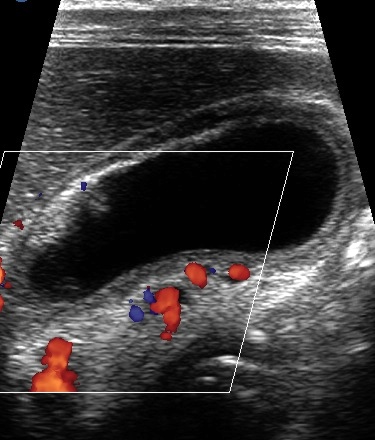

Gallbladder Wall Varices

Another set of collaterals in PV thrombosis includes gallbladder wall varices (GWV) (Figure 3) which are seen in 30 % of patients with PV thrombosis (Chawla et al.). These are portosystemic shunts between cystic vein branch of the PV either to systemic anterior abdominal wall veins or to the patent PV branches within the liver [14]. On sonography, the GWV appear as anechoic serpentine channels that show a continuous low velocity signal typical of portal venous system [14]. Their presence does not correlate with the site and extent of PV thrombosis [14]. The varices may reduce the distensibility of gall bladder [21] or can give rise to hemobilia or intra-abdominal hemorrhage. There is, however, no alteration in emptying of gall bladder or lithogenicity of bile [21]. Clinical implication of GWV include variceal bleed (seen in 1%) [22] and caution during biliary track surgeries for risk of hemorrhage.

|

Figure 3. Sonogram depicts dilated venous channels in the wall of gall bladder. |